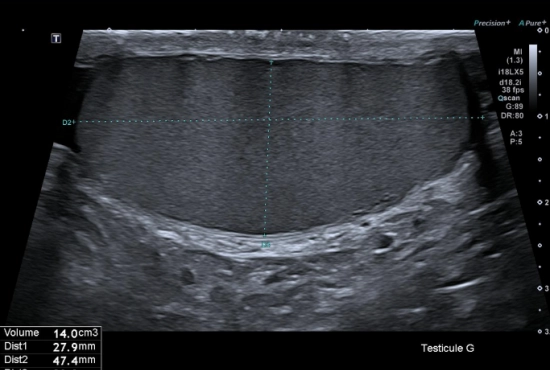

"Quand une douleur testiculaire cache une hernie inguinale : l'importance de l'exploration systématique des orifices herniaires"

25/04/2026

Lire la suite